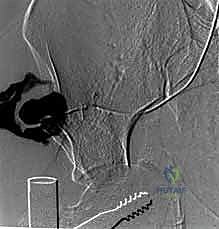

يتم الاستعانة بجهاز الأشعة السينية المتحرك داخل غرفة العمليات (C-arm Fluoroscopy) للتأكد من وضعية المسامير بدقة المليمتر، لضمان عدم اختراقها للأعصاب أو الأوعية الدموية.